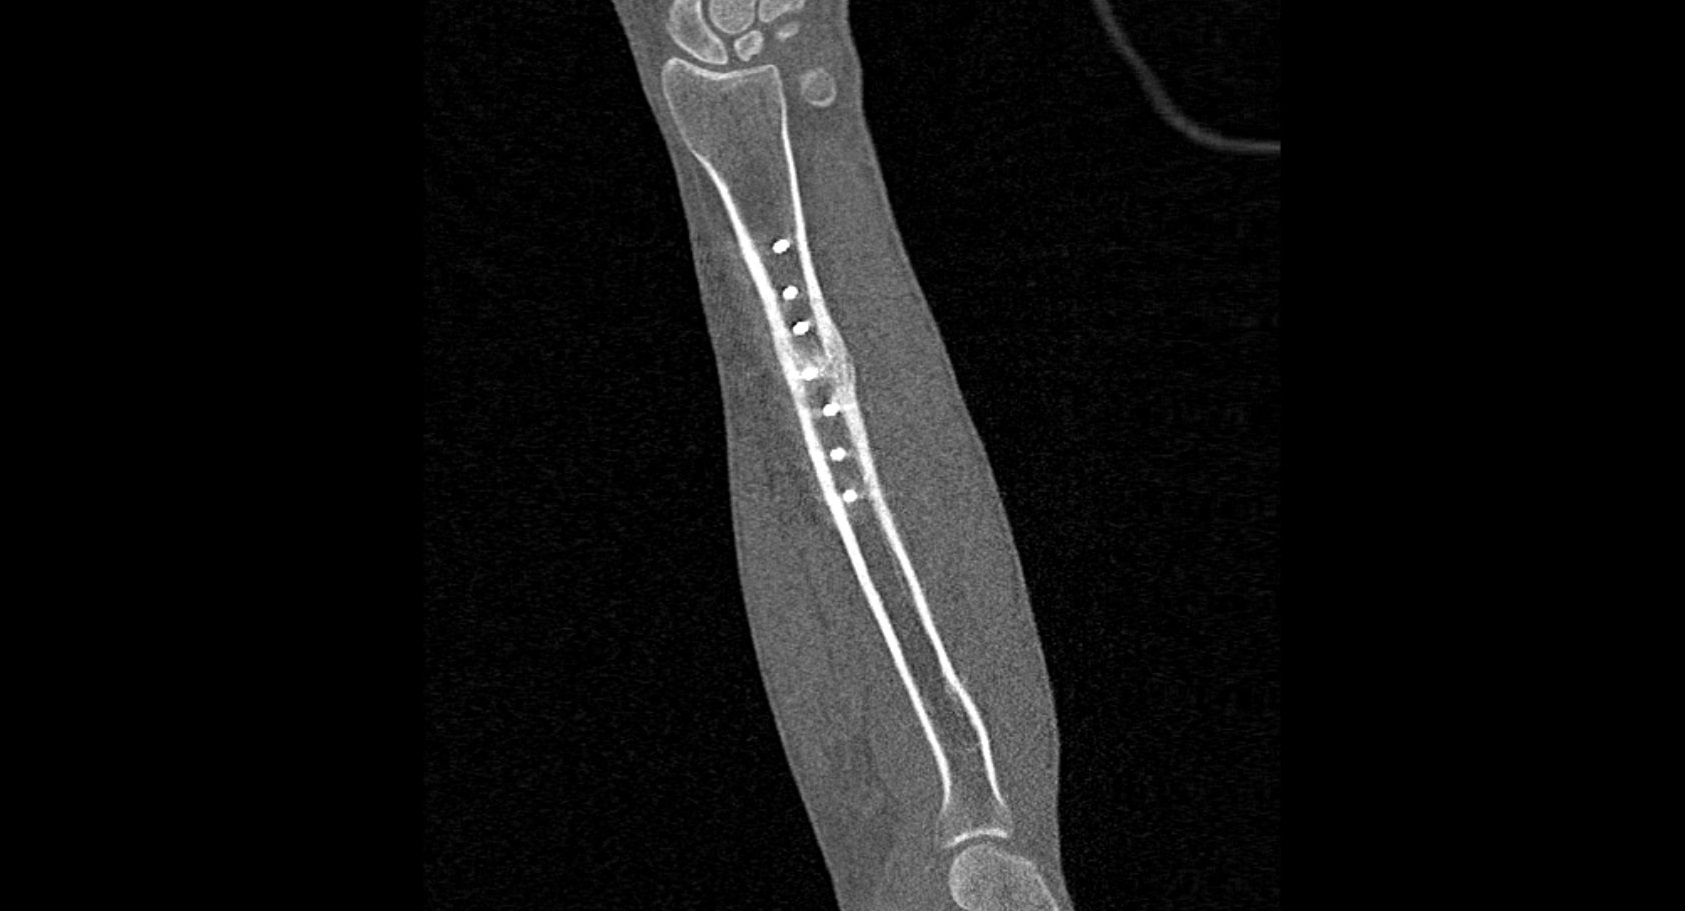

В диагностических центрах «Доступная медицина» сканирование области предплечья проводится на современных мультиспиральных компьютерных томографах экспертного класса TOSHIBA AQUILION. Аппараты при помощи рентгеновских лучей послойно сканируют исследуемую область, делая одномоментно множество тончайших срезов толщиной от 0,5 мм. В результате получаются детализированные изображения высокого уровня четкости и контрастности, при этом томографы обеспечивают минимум лучевой нагрузки на организм пациента.

Полученные при сканировании данные в дальнейшем проходят цифровую обработку, и на их основе создаются трехмерные изображения области предплечья.

Мультиспиральная КТ позволяет диагностировать деформации костей на фоне аномалий развития, различные вывихи, переломы костей предплечья, ушибы мягких тканей и надкостницы. КТ помогает обнаружить участки деструкции костной ткани, воспалительные изменения, опухолевые процессы. Результаты КТ дают информацию для хирурга и травматолога перед операцией о расположении осколков кости, а после операции позволяют оценить правильность репозиции костных отломков, проследить процессы регенерации кости, вовремя выявить различные осложнения (воспаление, смещение отломков, очаги деструкции костной ткани).